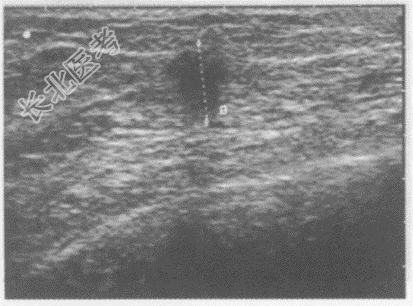

- 单项选择题临床资料:女, 39岁,常规体检。

超声综合描述: 右乳外上象限腺体层内可见1.4cm×1.2cm类圆形低回声区,边界清, 内回声不均。

超声提示: A、乳腺增生结节

B、乳腺纤维腺瘤

C、乳腺癌

D、乳腺囊肿

E、乳腺脂膜炎